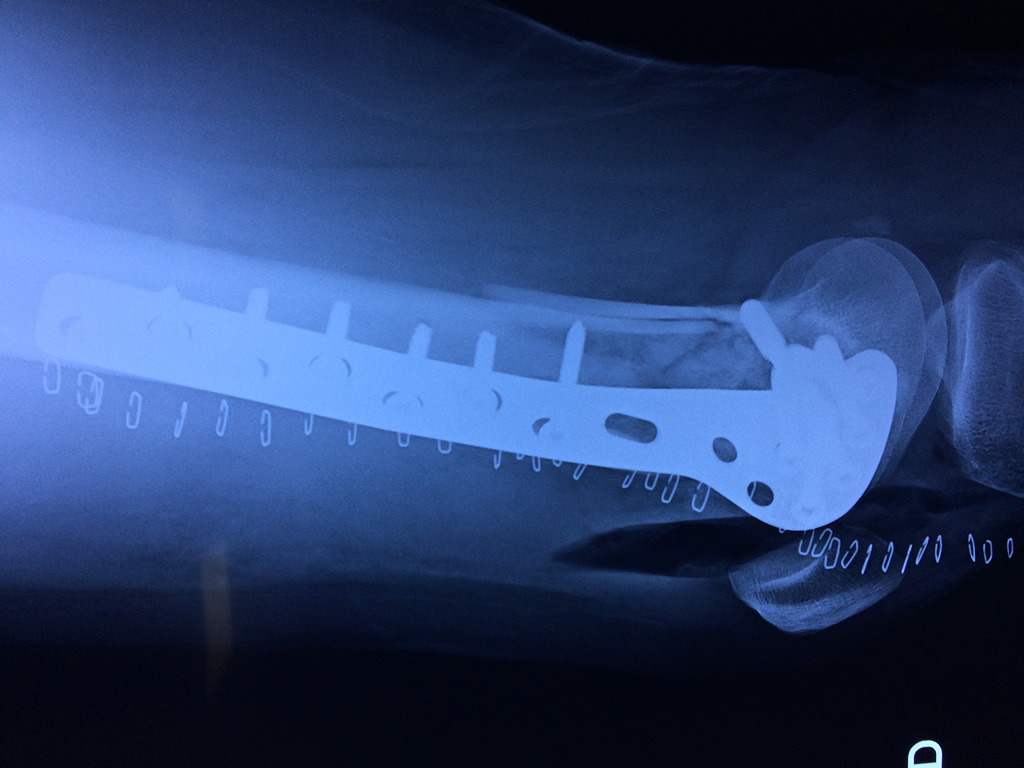

El fémur es el hueso del muslo, el segundo segmento del miembro inferior. Es el hueso más largo, fuerte y voluminoso del cuerpo humano.